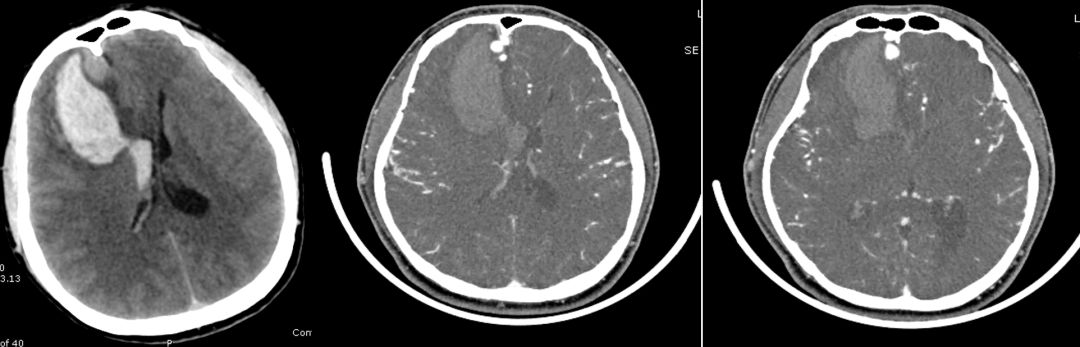

男性,37岁,头痛4天。既往体健。

答案:右侧额部动静脉瘘。

患者右侧额部血肿破入脑室,患者青年男性,既往体健,非高血压脑出血的常见部位。出血原因考虑动静脉瘘,前交通动脉瘤等。患者增强CT可见增粗的静脉血管影,考虑右侧额部动静脉瘘,患者经过DSA证实,见下图: